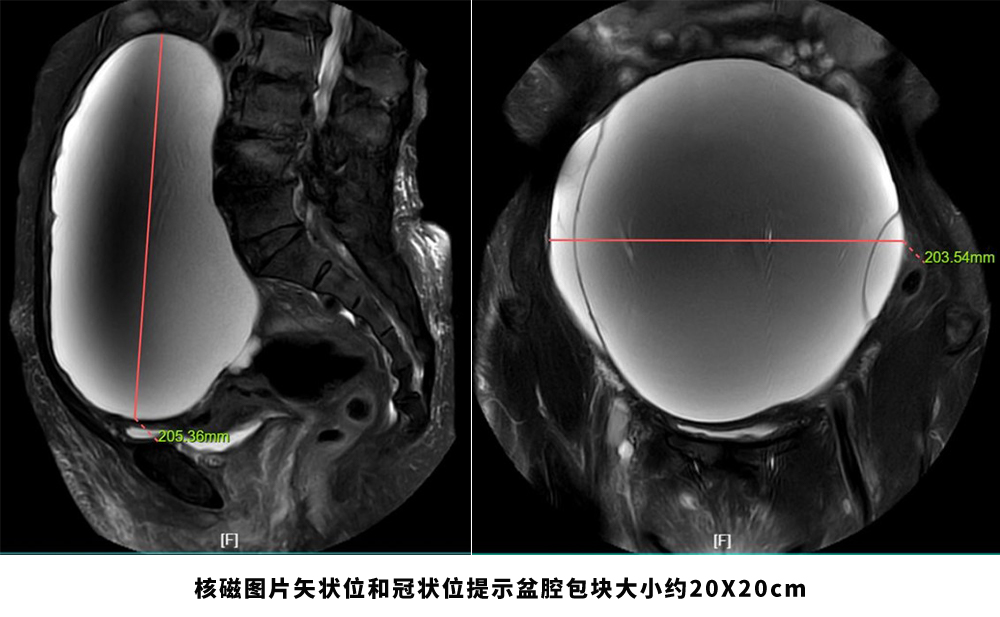

69岁的患者陈女士,2024年2月7日因“下腹隐痛6天”于当地医院就诊,经检查发现其盆腹腔可扪及一“如孕7月大小”的包块,考虑卵巢肿瘤,因患者合并肝硬化失代偿期等多种内科疾病,暂时无法手术,当地医生建议转至中南大学湘雅三医院妇科治疗。2月29日,患者首次来到湘雅三医院妇科,肖松舒教授在接诊后建议患者接受住院治疗;3月12日,患者办理入院后,肖松舒教授团队迅速为患者完善了相关检查。

经检查发现:患者病情复杂,全血细胞减少(血小板59×10^9/L、中性粒绝对值0.69×10^9/L、血红蛋白99g/l)、低蛋白血症及黄疸(白蛋白27.3g/L、总胆红素131.8umol/l、直接胆红素20.1umol/l)、凝血功能障碍(凝血酶原时间20.1sec、纤维蛋白原浓度0.83g/l、凝血酶原活动度42.3%)、肝硬化失代偿期、肝硬化并门静脉高压、门静脉血栓形成、脾亢、肺部感染等多种疾病,卵巢巨大肿瘤与多系统功能障碍交织使得治疗难度极大,手术风险极高。